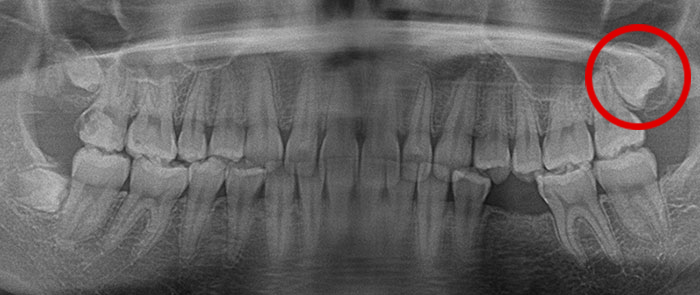

真横になった親知らずを抜歯したレントゲン写真です。